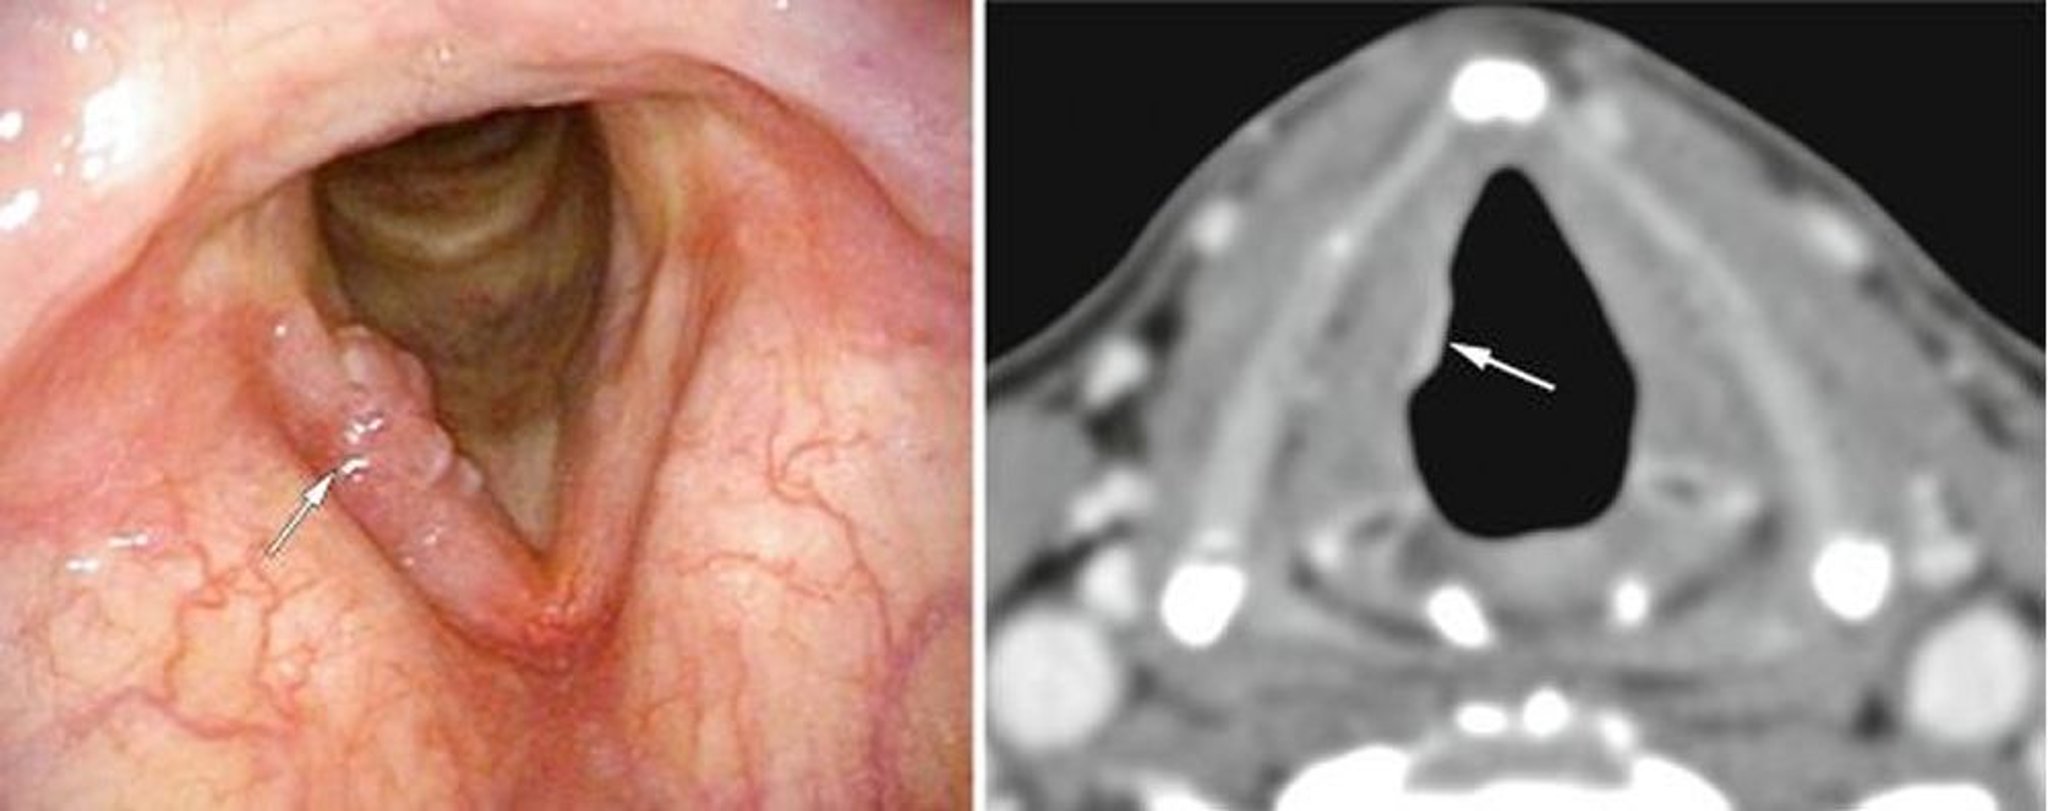

Cancer précoce du larynx

Ce patient avait un cancer laryngé glottique précoce, visible ici sur une corde vocale à l'endoscopie (image de gauche, flèche blanche) sous forme d'excroissances et sur la TDM (image de droite, flèche blanche) sous la forme d'une densité anormale des tissus mous.